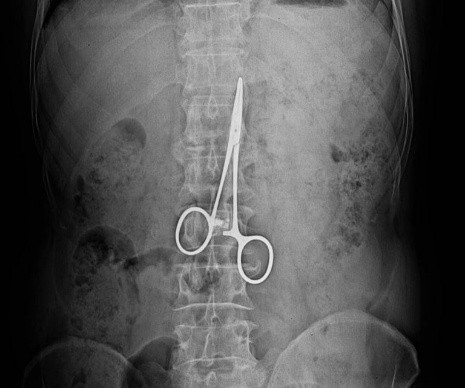

Диагностика рентгенпозитивных инородных тел успешно проводится с помощью традиционной рентгенографии и ультразвукового исследования (УЗИ) .

Рентген -диагностика.

Выявляется:

- дополнительная тень в зоне интереса;

Особая категория инородных тел в организме человекам – это инородные тела, оставленные в результате хирургических вмешательств. Это относительно редкое осложнение. До 50% всех инородных тел составляют забытые хирургические тампоны, марлевые салфетки дренажные трубки, фрагменты катетеров, хирургические инструменты. Чаще всего инородные тела остаются после полостных операций, реже – после лапароскопических, эндоскопических, чрескожных. Наиболее распространенными локализациями ИТ являются брюшная полость, полость таза, также описаны случаи их нахождения в грудной, плевральной, перикардиальной полостях, забрюшинном пространстве, полости черепа, мягких тканях.